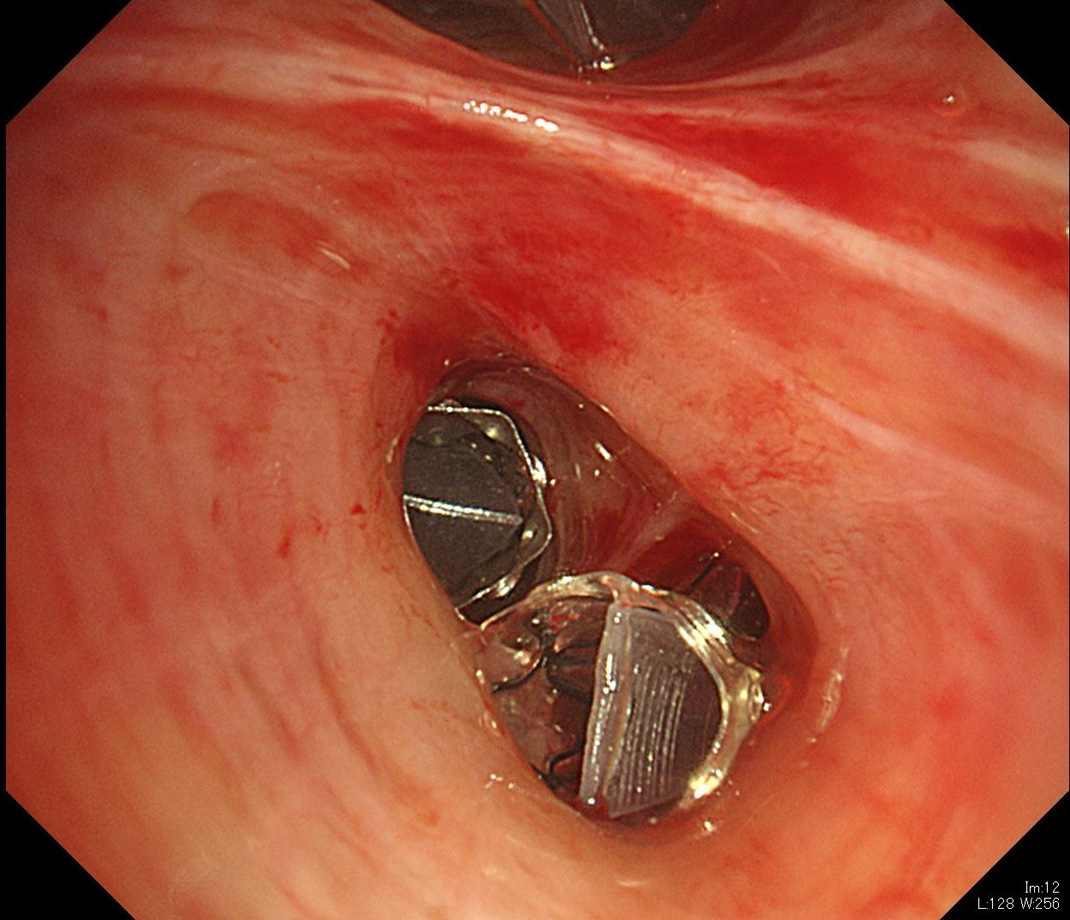

気管支鏡を用いて気管支内にバルブを留置する気管支鏡的肺容量減量術(BLVR)により、過膨張した肺を縮小させ、呼吸機能や息切れの改善を図ります(図5)。本治療は保険適用されていますが、現在、全国で施行可能な施設は14施設のみで、岐阜県内では当科が唯一の実施施設です。

図5 気管支バルブ:標的気管支に気管支バルブが留置されています。